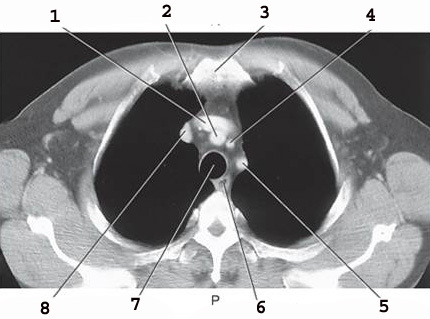

1

L common carotid Artery

2

L subclavian artery

3

AO arch

4

ascending AO

5

SVC

6

Brachiocephalic trunk

7

R subclavian vein

8

R subclavian Artery

9

R common carotid A